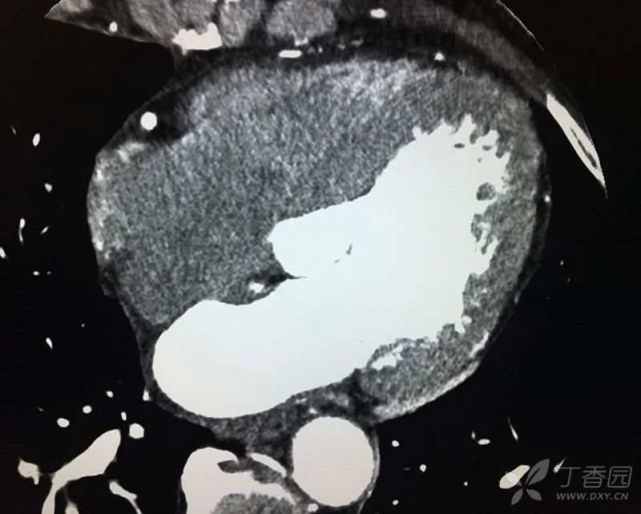

2016 年 2 月患者因「腹胀腹痛 3 d」入住我院普外科。查上腹部 CT 示:脾大、脾破裂、腹腔积液、积血(图 5)。行脾切除术,术后恢复顺利,很快出院。住院期间首次发现肝酶升高:生物化学:ALT 22 U/L,AST 28 U/L,ALP 190 U/L,GGT 323 U/L,TBil 6.6 μmol/L,DBil 2.7 μmol/L,CREA:66 μmol/L。

图片

(图 5 上腹部 CT 图)